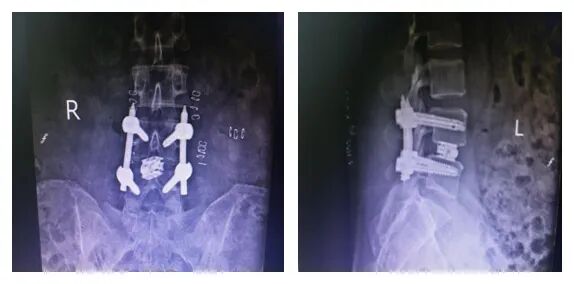

術(shù)后照片

PE-TLIF技術(shù)是一種微創(chuàng)椎間融合技術(shù),手術(shù)方案為經(jīng)椎間孔入路,使用上關(guān)節(jié)突導(dǎo)向切除裝置定向磨除上關(guān)節(jié)突,擴(kuò)大椎間孔區(qū)域,在直徑僅7毫米的脊柱內(nèi)窺鏡輔助下進(jìn)行腰椎的減壓、椎間植骨及融合器植入,最后輔以經(jīng)皮置入椎弓根螺釘。該技術(shù)通過較小的創(chuàng)傷,既能達(dá)到與開放腰椎減壓融合手術(shù)同樣的臨床效果,又能減少并發(fā)癥,實(shí)現(xiàn)病人快速康復(fù)的目的。

患者術(shù)后2天下地行走